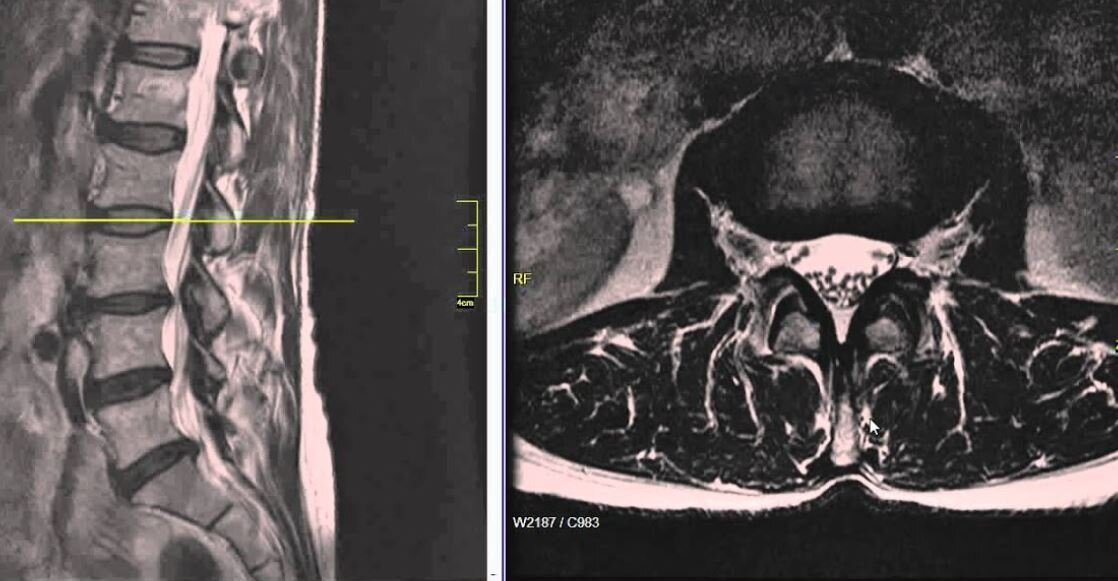

You and Your MRI

mr.JPG

This program will illustrate common MRI findings and discuss what they mean and what they DON’T.

Although MRI’s can be helpful, they can also lead to needless fear and receiving inappropriate treatment.

Numerous scientific studies have clearly shown that a large number of people who have NEVER had low back pain will have abnormalities on their MRI. Because of this, it is important to know how to use your MRI results in a way that they help you, rather than work against you. This session will do that for you and, as with my other presentations, you will have plenty of time to ask your own questions.

You and your MRI. click here to be notified about next session